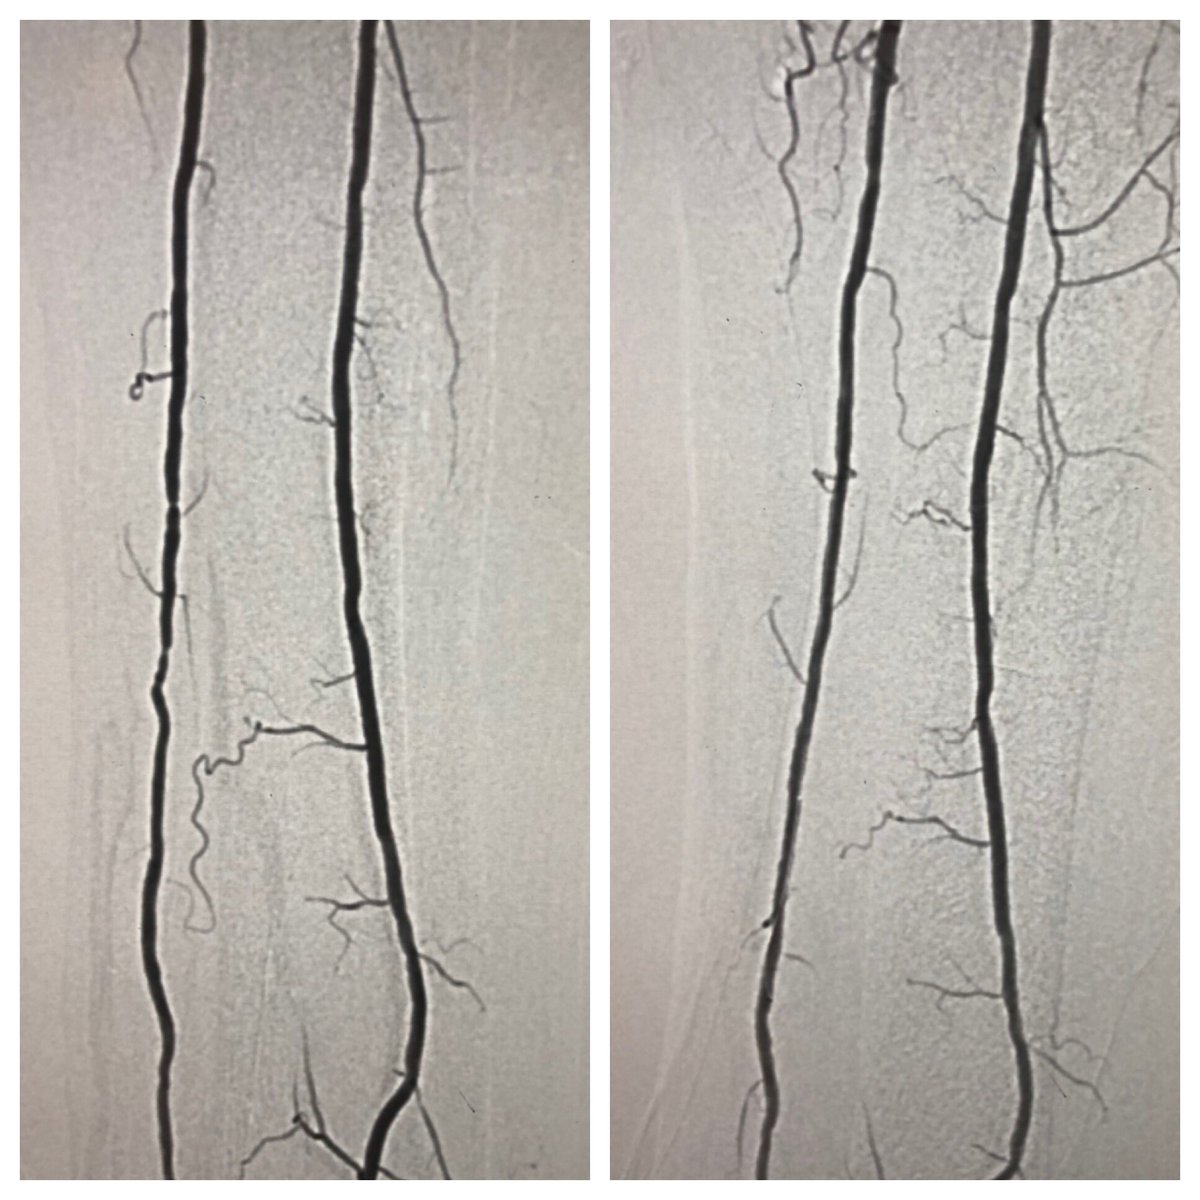

Late case before time off for the 4th! Open toe wound w/ osteo. Antegrade crossing of occluded peroneal. Tibial access to cross long segment ATA occlusion after failed antegrade attempt. Initial access too close to distal cap so moved distal #CLI #SCAIPAD #wifeissounderstanding